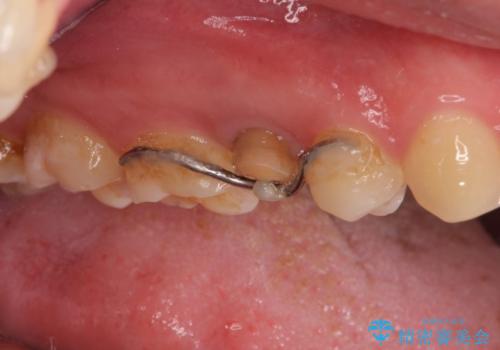

右上の被せものを除去したところ、中で歯が割れていたため、部分矯正で引っ張り出すことになりました。

・約3か月ほど引っ張り出します。

・両どなりの歯に一時的にワイヤーを接着します。

・十分に引っ張り出した後、歯肉の手術が必要となります。

・歯肉が落ち着いてから最終的な被せものの製作となります(約3か月)。